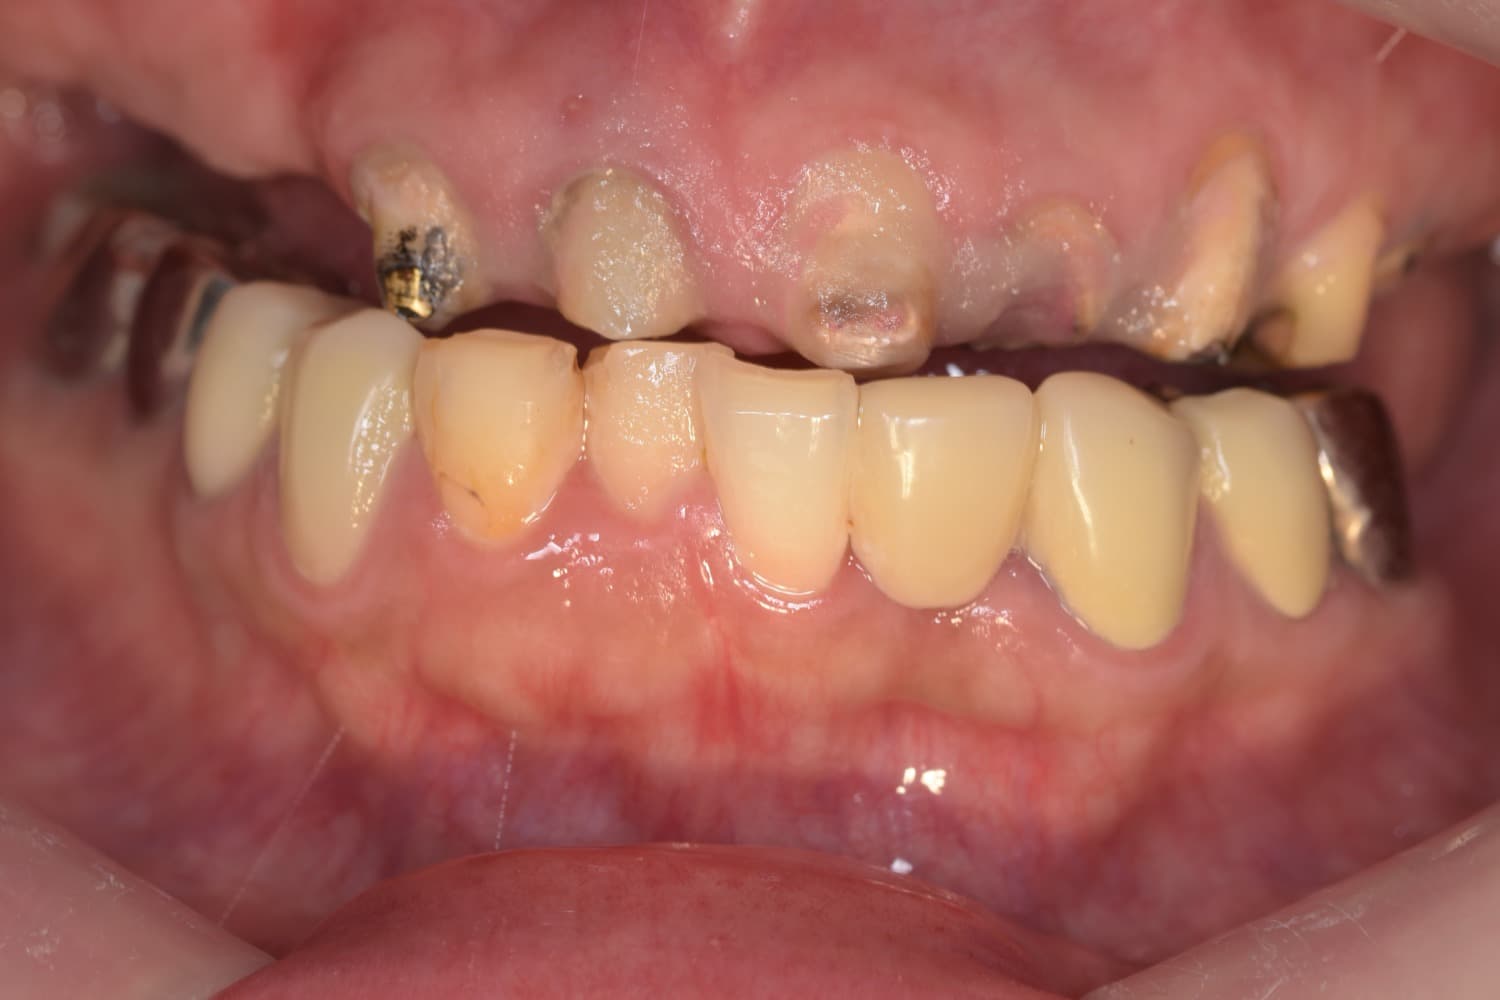

上顎の全顎の即時インプラント(40代女性)

Before

上顎の全顎の即時インプラント(1Dayトリートメント) 仮歯まで1日で入ります。 ※治療後も定期的なメンテナンスは必要

年齢

40代

性別

女性

主訴

歯が欲しい、インプラントを入れたい

治療期間

3ヵ月

治療回数

5回

費用

300万円

副作用・リスク

顔面の腫れ